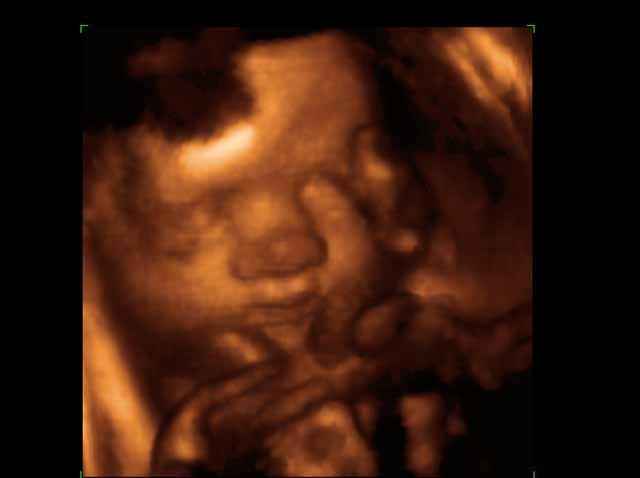

- صور لوجه الجنين في داخل الرحم

صور لوجه الجنين بجهاز الالتراساوند ثلاثي الأبعاد | الدكتور نجيب ليوس